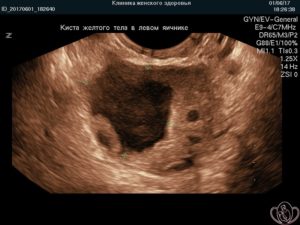

УЗИ снимок кисты желтого тела.

- УЗИ. В полости кисты отсутствуют кровеносные сосуды. Это является отличительной характеристикой лютеинового новообразования.

Интересно, что согласно статистике киста желтого тела чаще всего формируется в области левого яичника.

Уточнить диагноз позволяет УЗИ.

Анатомические особенности женского организма предполагают, что чаще лютеиновое новообразование поражает левый, чем правый яичник.